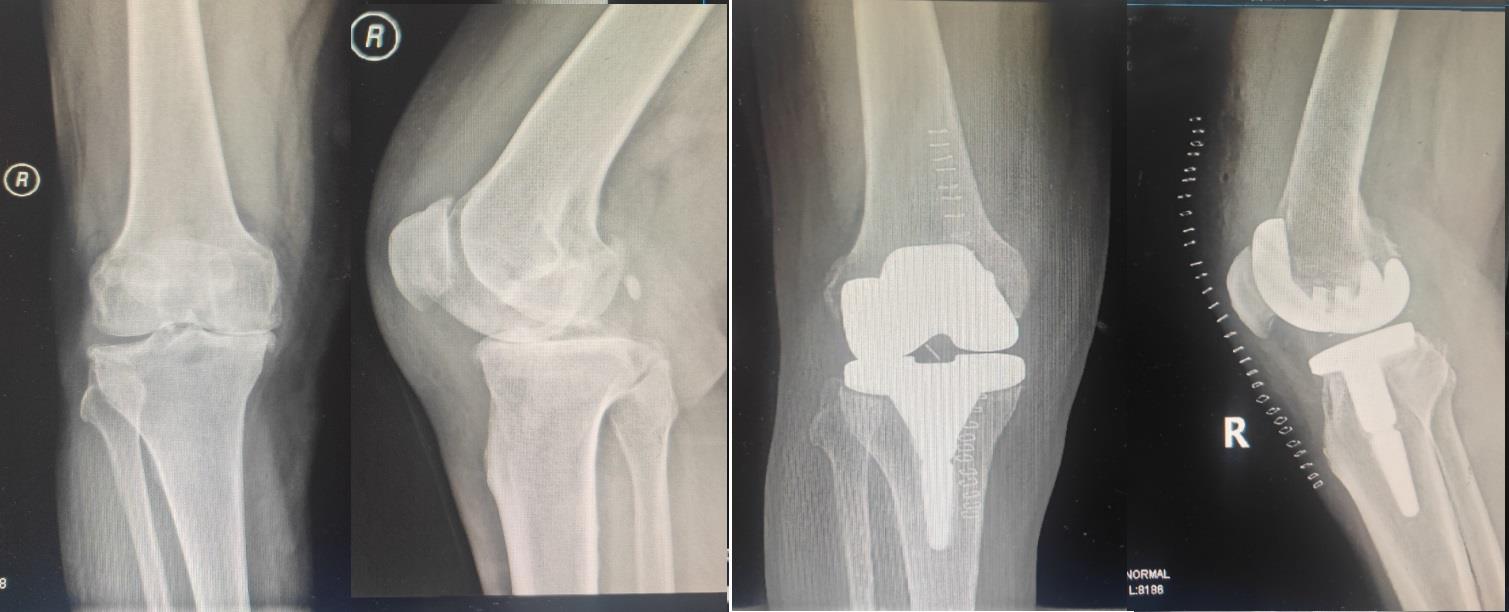

目的 比较CR假体与PS假体在人工膝关节置换术后应用效果。 方法 随机选取2021年6月至2022年6月在我科收治且符合选择标准的膝骨性关节炎患者64例,随机分为观察组和对照组(n = 32)。观察组使用CR假体实施TKA,对照组使用PS假体实施TKA。记录两组患者的手术时间、术后引流量、手术前后HGB差值、术后住院时间,术后7 d、14 d、45 d、3个月、1年膝关节ROM、VAS评分、HSS评分、膝关节最大前后向位移,并定期复查X线片。 结果 两组患者在手术时间、术后住院时间、VAS评分、膝关节最大前后向位移方面相当;和对照组相比,观察组术后引流量明显更少,差异有统计学意义(P < 0.05);和对照组相比,观察组在HGB差值上明显更低,差异有统计学意义(P < 0.05);手术之前两组患者ROM、HSS评分无明显差异,和观察组比较,术后7 d、14 d、45 d时对照组ROM以及HSS评分更高,差异有统计学意义(P < 0.05),术后3个月时,两组ROM、HSS评分相当,术后6个月、1年时观察组的ROM、HSS评分明显更高,差异有统计学意义(P < 0.05)。 结论 CR假体在手术失血量和术后引流量方面优于PS假体,可以降低手术风险,两种假体在术后均可获得良好的膝关节稳定性,而PS假体早期临床效果较好,CR假体长期临床效果更优。

Objective To compare the effect of posterior cruciate ligament retaining (CR) and posterior cruciate substituting (PS) prosthesis in knee arthroplasty. Methods 64 patients with knee osteoarthritis were admitted to our department from June 2021 to June 2022 and whom met the selection criteria were randomly selected and divided into observation group and control group (n = 32). CR prosthesis was used in the observation group, and PS prosthesis was used in the control group. Operation time, postoperative drainage volume, difference of hemoglobin (HGB) before and after operation, postoperative hospital stay, postoperative range of motion at 7 d, 14 d, 45 d, 3 months and 1 year were recorded. ROM, visual analog pain Scale (VAS), Hospital for special surgery (HSS) score, and maximum forward and backward displacement of knee joint and the regular radiographs were also recorded, too. Results The two groups were similar in terms of operation time, postoperative hospital stay, postoperative VAS score and maximum anterior and posterior displacement of knee joint, with P values greater than 0.05, which had no statistical significance. The postoperative drainage volume in the observation group was significantly less than that in the control group, with statistical significance (P < 0.05). The HGB difference of observation group was significantly lower than that of control group, with statistical significance (P < 0.05). There was no statistically significant difference in ROM and HSS scores between the two groups before surgery; the ROM and HSS scores of the control group at 7, 14 and 45 days after surgery was better than that of the observation group, with statistical significance (P < 0.05); the ROM and HSS scores of the two groups at 3 months after surgery was not statistically significant. The ROM and HSS scores in the observation group was better than that in the control group at 6 months and 1 year after operation, and the difference was statistically significant (P < 0.05). Conclusions CR prosthesis is superior to PS prosthesis in terms of intraoperative blood loss and post?operative drainage volume, which can reduce surgical risk. Both kinds of prosthesis can achieve good knee stability after surgery, while PS prosthesis has better early clinical effect, while CR prosthesis has better long?term clinical effect.